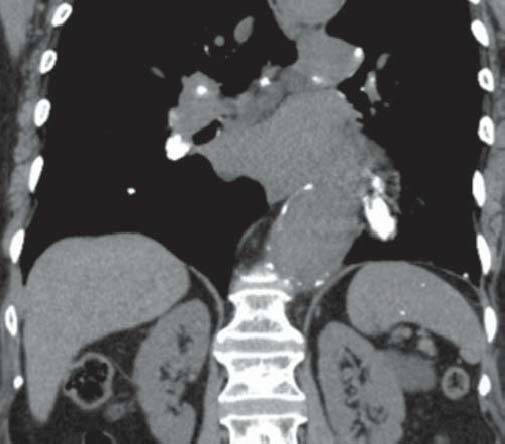

男性,48岁,以肺结节就诊。

C

图A和B为轴位CT平扫,示肝、脾内多发大小不一的钙化,肝、脾大小形态正常,图C和D为冠位重组纵隔窗及肺窗,示纵隔、肺门淋巴结钙化及肺的钙化结节,同时发现主动脉瘤。

组织胞楽菌病是美国中部的一种地方病,自艾滋病流行以来,本病发病率明显上升,在非流行地区也有报道。大多数组织胞浆菌病患者伴有纵隔淋巴结肿大、钙化(如本例所示),可引起纵隔压迫症状。患者腹部CT扫描可见散布的组织胞浆菌病,肝大(63%)、脾大(38%)、弥漫性脾密度减低(19%)、双侧肾上腺肿大、淋巴结肿大(44%)。在美国,治愈的组织胞浆菌荚膜感染是引起弥漫性脾钙化的最常见原因,引起多发脾钙化的其他原因有治愈的结核、布鲁杆菌病及肺囊虫感染、血管瘤、静脉石、含铁血黄素沉着症、镰状红细胞贫血和含铁结节(G-G小体)。